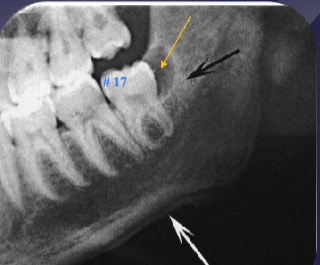

what is the black arrow pointing to

large sequestra caused by acute osteomyelitis

what are the arrows pointing to

fistula due to acute osteomyelitis

what is the white arrow pointing to

periosteal reaction due to acute osteomyelitis